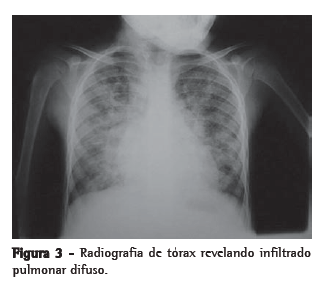

Para ilustrar a utilização do líquido de LBA no diagnóstico de afecções pulmonares, exibe-se a seguir a imagem radiológica (Figura 3) e do líquido de LBA (Figura 4) que auxiliaram no diagnóstico de hemossiderose pulmonar em uma criança com histórico de hemoptise e anemia ferropriva.